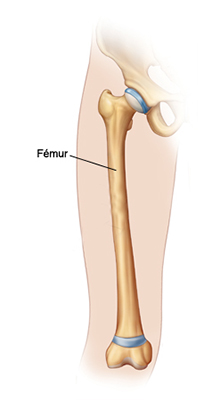

El fémur es el hueso del muslo, el segundo segmento del miembro inferior. Es el hueso más largo, fuerte y voluminoso del cuerpo humano.

El fémur es el hueso del muslo, el segundo segmento del miembro inferior. Es el hueso más largo, fuerte y voluminoso del cuerpo humano.

El fémur es el hueso del muslo, el segundo segmento del miembro inferior. Es el hueso más largo, fuerte y voluminoso del cuerpo humano.

El fémur es el hueso del muslo, el segundo segmento del miembro inferior. Es el hueso más largo, fuerte y voluminoso del cuerpo humano.